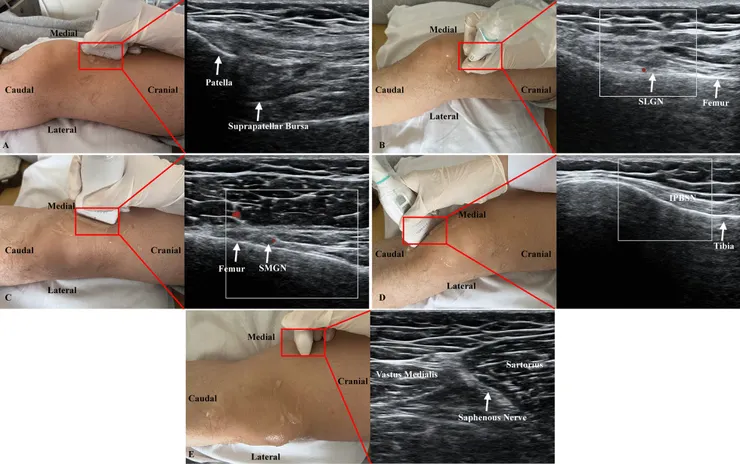

但這第二篇文章他就真是把20%葡萄糖8ml平A進去了--會注射到 8ml 這麼多是因為關節囊的大小,照理而言在關節囊內引動發炎應當會是更痛的;作為對照的是周邊四條神經的5% 2ml 葡萄糖浸潤。

分開看的話對於疼痛、WOMAC 量表與壓痛閾值,關節內注射的效果沒有神經浸潤來的快,但到了一兩個月後效果會逐漸出來,可能代表這是由不同的機制產生 (如周遭韌帶強化),但整體而言是關節內外都打會比較好。

ㄟ對,我真的在閱讀了此文章後接下來分別選了好幾個滑膜增生反覆長水的人進行了關節內20%葡萄糖注射。收進測試前都先排除了痛風病史,大部分有關節受傷後開始反覆積水的病程,少數是被診斷類風溼性關節炎而關節反覆長水,收案標準是反覆長水超過三個月,曾經打過類固醇關節內注射,但間格沒有超過三個月就又大量長水,超音波下看到嚴重滑囊增生。在採用此治療前已先完整告知此療法非正規療法、若裡面是結晶性關節炎可能會更為嚴重。

整個療程裡面「目前選到的每一個」都是從可以兩個星期到一個月抽個20、30ml開始,每兩周抽乾後注射8ml 20%葡萄糖,接著就看到水越來越少、滑膜厚度下降。然後膝蓋穩定性上升,疼痛感下降會出現在第一個月之後,我個人認為很有可能跟關節內的穩定性組織(如韌帶)被增生療法穩固有關。至於這會不會是自然病程?當然在一些年輕人身上無法排除,但若反覆發作加上滑膜增生的患者也有療效反應,我認為是可以適當選定患者嘗試治療的。